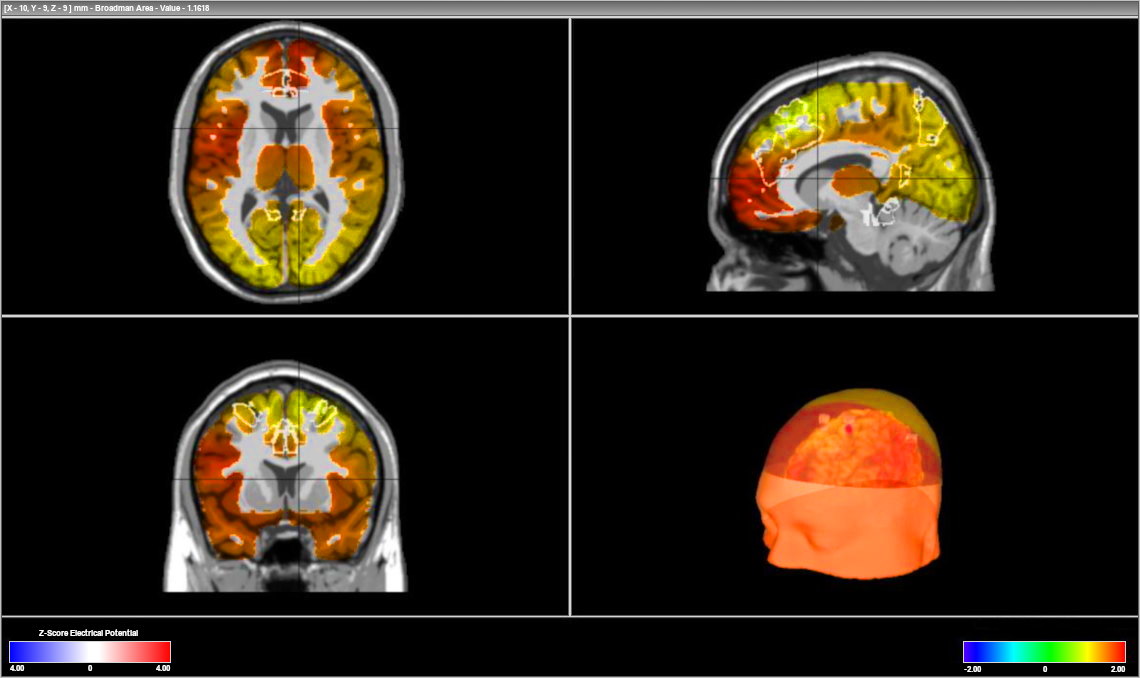

The process of Neurofeedback training begins with an intake session where we will complete what we call a "brain map" of 19 brain locations (also called a qEEG). First, sensors from our a state-of-the-art 19 point EEG equipment are positioned on the scalp and ears (the sensors are non-invasive and painless). During the brain mapping process your brain's electrical activity is measured while you perform some simple mental tasks. We monitor and record your brain wave activity and feed the information into a computer. The computer software will analyze the amplitude and location of your brainwaves and create a 3 dimensional brain map.

We also analyze and compare your brain wave patterns to a normative database of brainwaves. Our software will generate an analysis that will assist us with identifying any brain wave irregularities that are present and the degree of severity.

A 3 dimensional brain map image of brain activity levels at different frequencies.